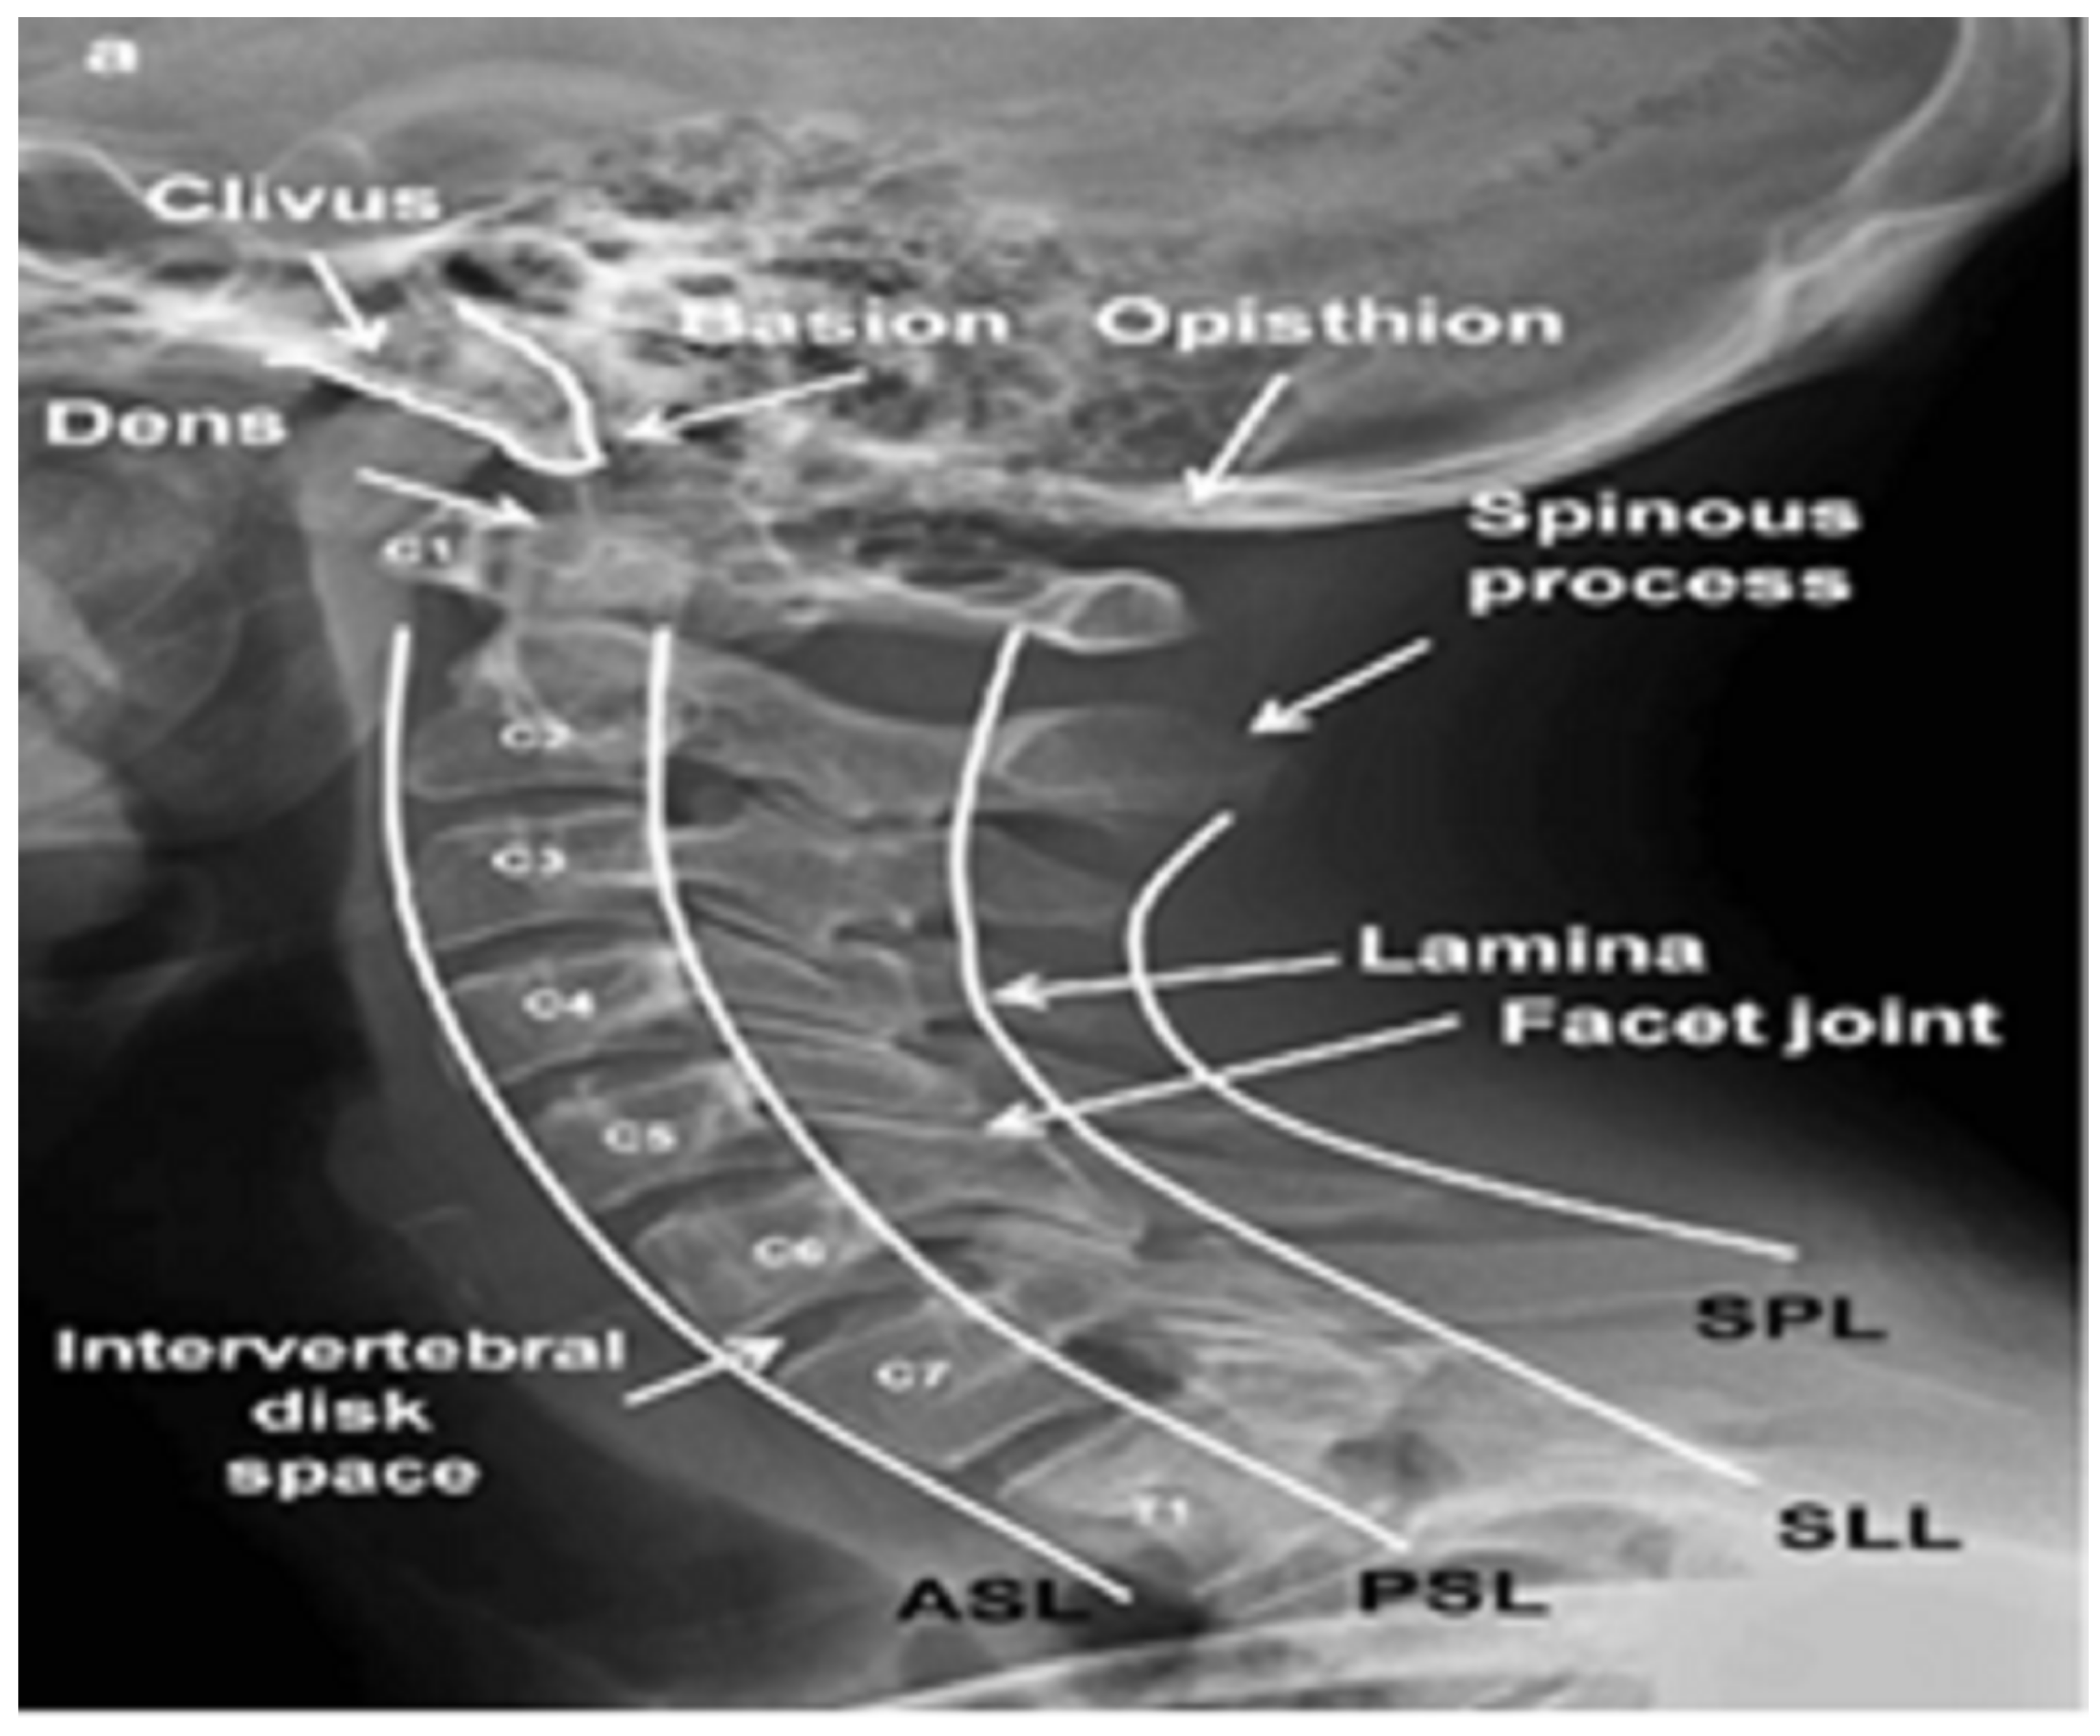

1. Introduction

2. Materials and Methods